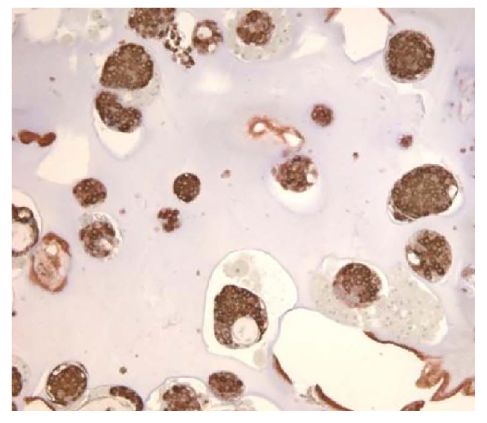

Paraffin embedded explanted islet slab was stained with anti-insulin followed by Goat Anti-Mouse IgG1, Human ads-HRP (SB Cat. No. 1070-05) and developed with DAB.